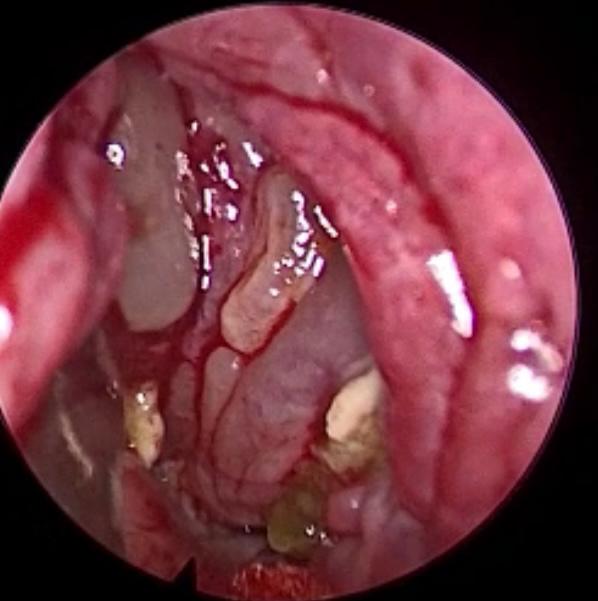

وأضاف الدكتور الحياري : بعد الفحص السريري والتنظير ، والفحص الشعاعي متعدد الجوانب ، تبين وجود التهابات على شكل تكتلات ، في جميع الجيوب الأنفية للجهة اليسرى ، من الوجهة مع وجود علامات لاحتماليه التهابات فطريه ، وبناء عليه تم ادخال المريض إلى غرفه العمليات.

وقال د. الحياري : مع تقدم العلم أصبح هنالك طرق حديثة لعلاج التهابات الجيوب الأنفية المزمنة ، وذلك عن طريق استخدام المنظار ، حيث تكون الرؤيا أوضح لطبيب الجراح والوصول للأماكن البعيدة في قاع الجمجمة ، بشكل اسهل وأدق وبدون حدوث أي مضاعفات للمريض.

وتابع قائلا : لقد تم استخدام المنظار مع اجهزه خاصه ، لتنظيف الجيوب حيث تم الدخول عليها ، وتنظيفها من الالتهابات الفطرية المتراكمة بدقه ، وبدون اي ايذاء للعين وقاع الجمجمة.